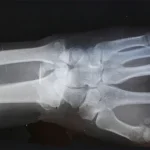

Bone Fractures

Detection of broken bones in any part of the body, including hairline fractures, displaced fractures, and stress fractures common in athletes and active individuals.

Osteoarthritis

X-ray shows joint space narrowing, bone spurs (osteophytes), and changes in bone density that indicate degenerative joint disease, commonly affecting knees, hips, and hands.

Wear comfortable, loose-fitting clothing without metal components such as zippers, buttons, snaps, or underwire. For a chest X-ray, a plain cotton t-shirt without prints or embellishments is ideal. For limb X-rays, wear clothing that allows easy access to the area being scanned, such as shorts for a knee X-ray or a short-sleeved top for a shoulder X-ray. You will be asked to remove all jewelry, watches, piercings, and hair accessories from the scan area. In some cases, you may need to change into a hospital gown to ensure the highest image quality.